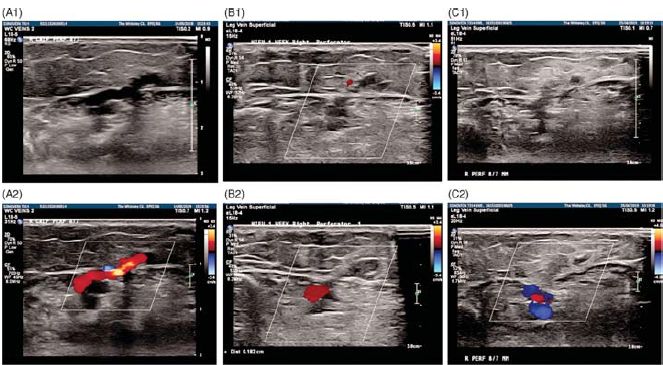

4. ábra.

Szürkeárnyalatos (A1, B1 és C1) és színes ultrahang képek (A2, B2 és C2) egy elégtelen perforans véna kezeléséről:

(A) kezelés előtt, (B) egy héttel a kezelés után és

(C) 6 héttel a Sonovein HIFU kezelést követően. (Prof. Dr. Mark Whiteley engedélyével)